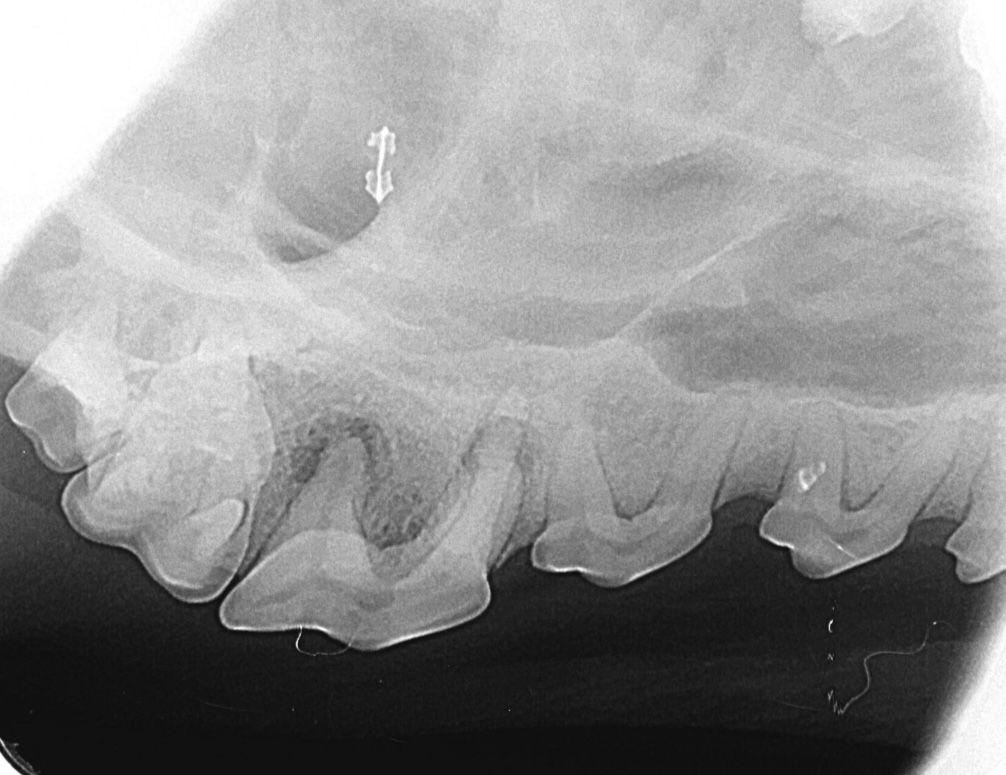

Radiographie dentaire

Réalisée sous anesthésie générale, la radiographie dentaire intra-orale permet d’évaluer les racines dentaires, l’os alvéolaire et les structures péri-apicales. Elle est indispensable pour détecter les lésions endodontiques, résorptions dentaires, pertes osseuses parodontales, fractures radiculaires ou dents incluses, et ainsi établir un diagnostic précis et fiable.